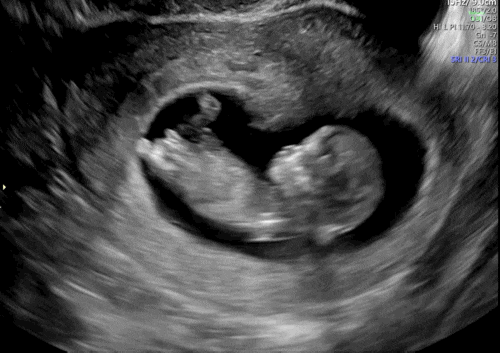

임신 10주 초음파 움직이는 모습 첫 발견! 땡큐 성장 기록 일기

9주 6일에 병원에서 초음파 보고 딱 10주되는 날 쓰는 일기? 출산 예정일이 2025년 1월 27일이었는데, 2...